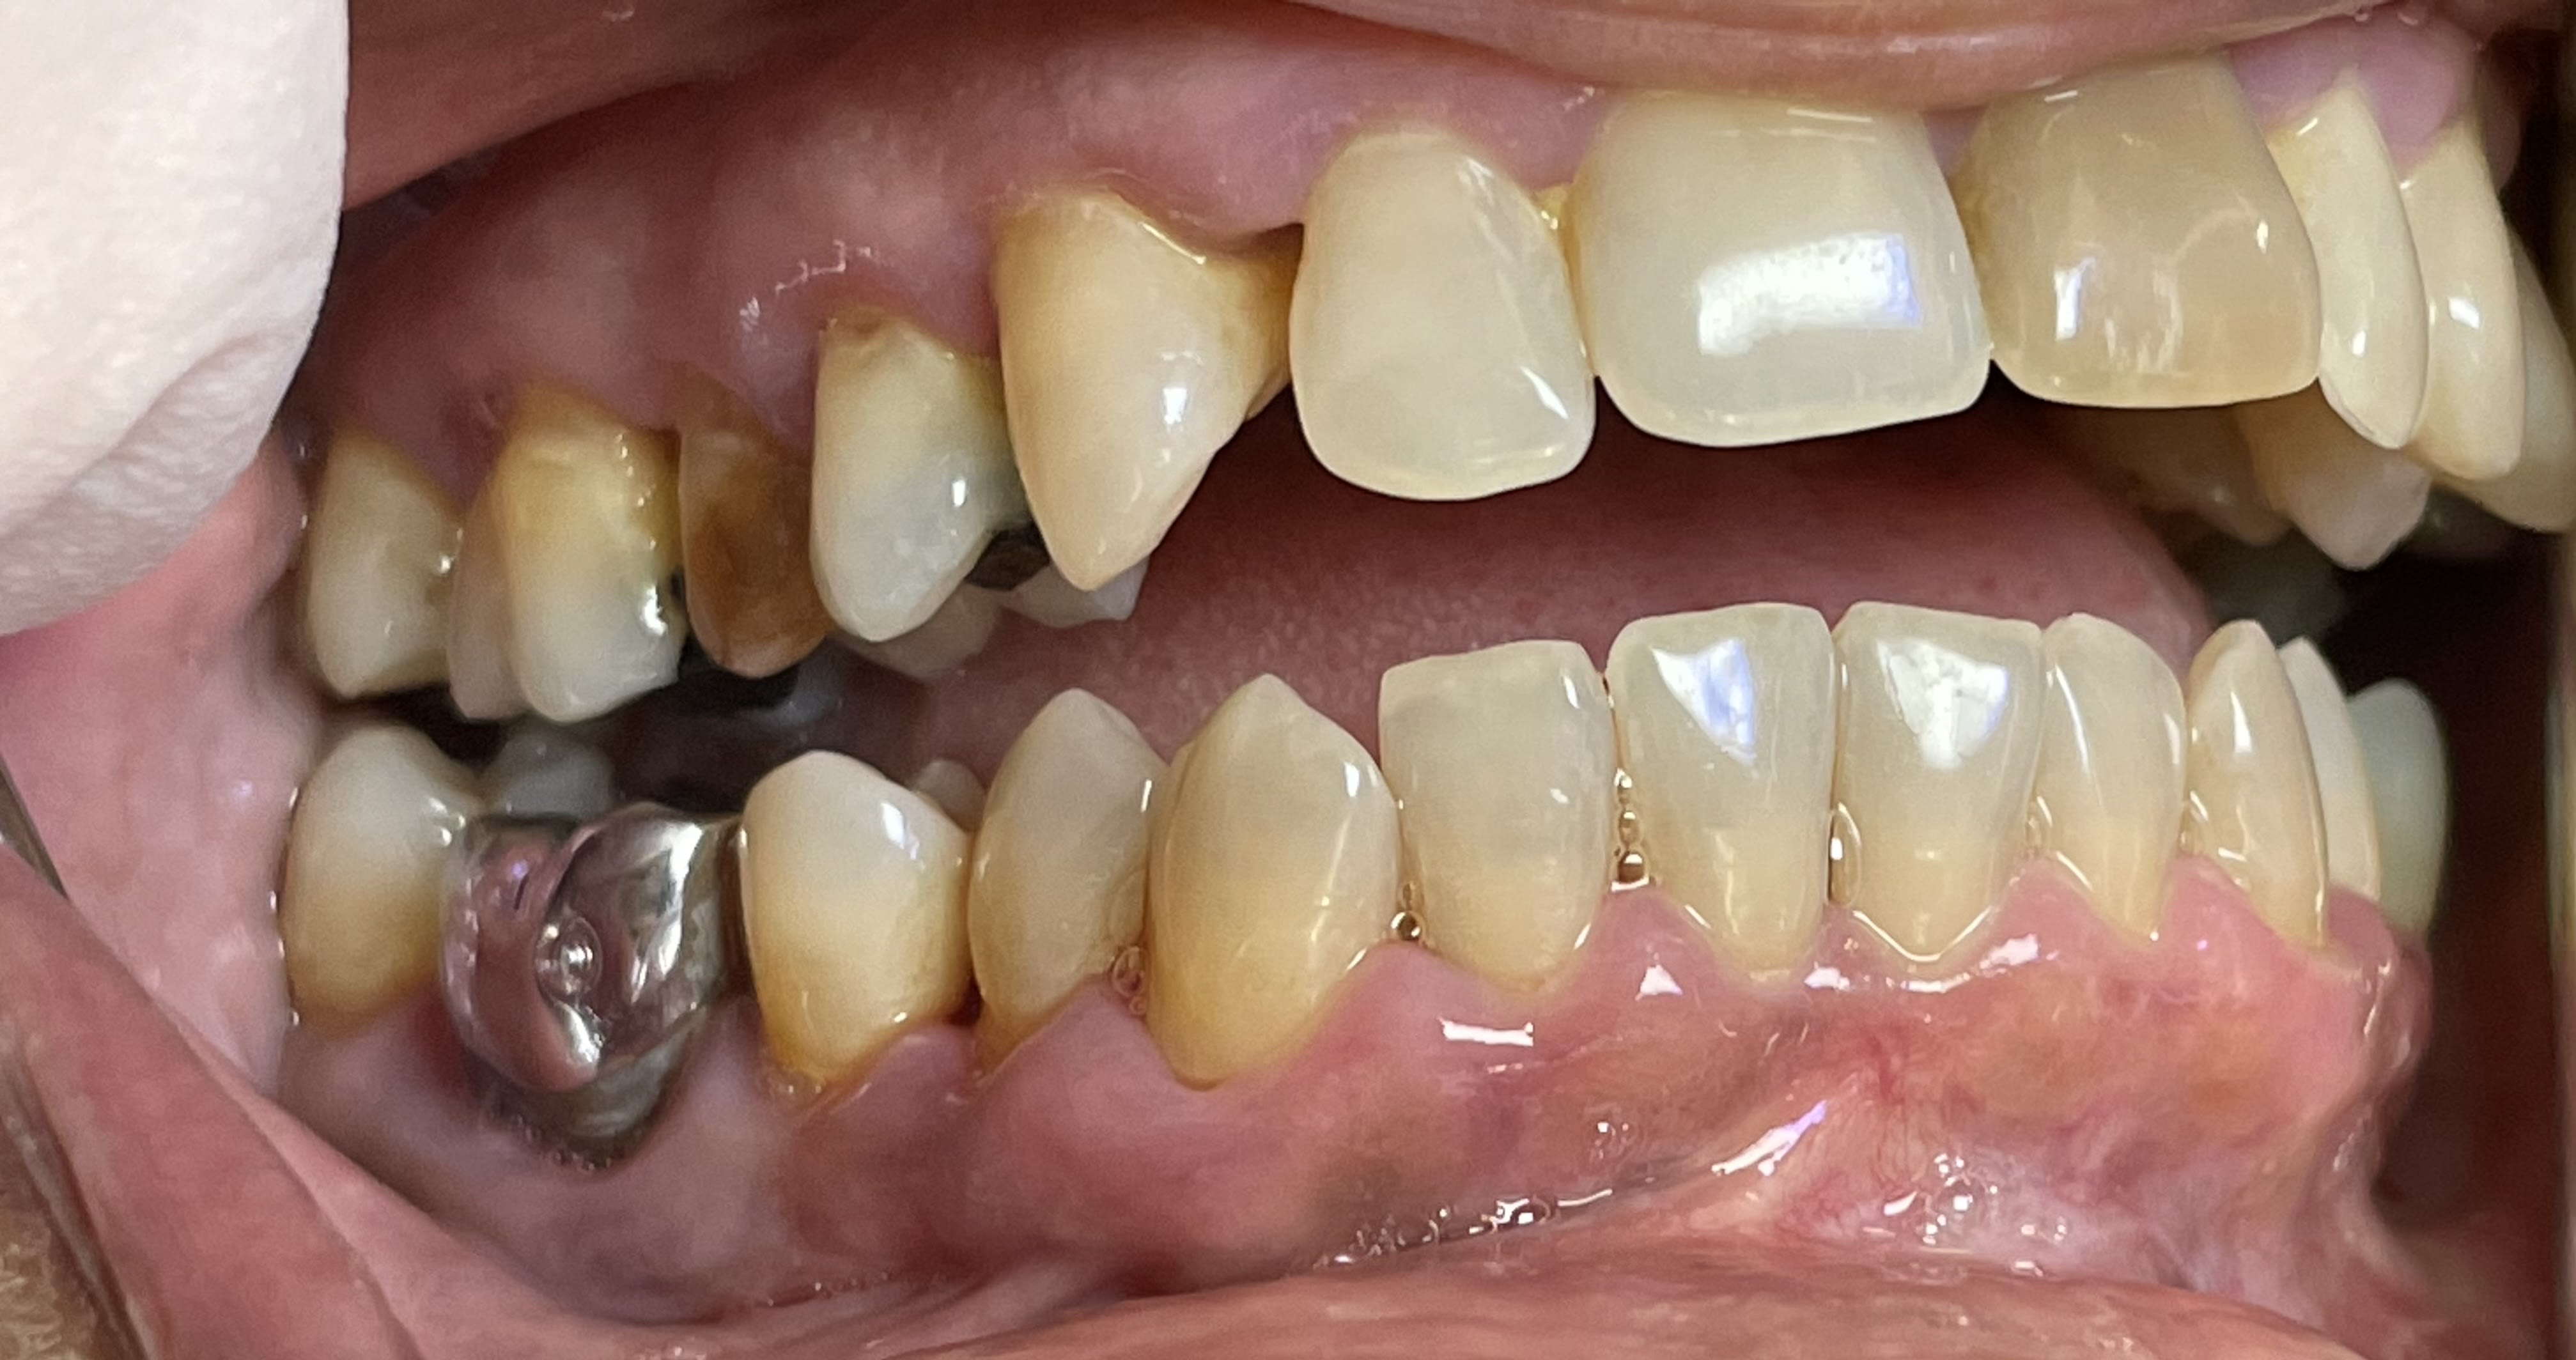

Abeba8c6 3e11 41b8 92b0 67fcd20541e8 eo52uo - Eugenol

41c944f7 8122 4b5e a226 53023e63b627 x9qrwr - Eugenol

Et là elle est en occlusion ? costaud ! Abus de gouttière ??

Port d'une OAM depuis plusieurs années ?

Je n’ai pas compris l’origine du problème. Peut être qu’elle a calé sa langue entre ses dents sauf au niveau des 7...

Ils lui ont viré 36 37 au passage

=> peut-être douleur articulaire avec éventuellement luxation

=> apposition de sa langue pour relâcher la pression

=> et répercussions sur l’occlusion au final

secteur 30 elle est etait genre occlusion croisée , probablement en beance , puis elle a perdu son calage post 36,37 ?

avec en plus une grosse interference 47 ?

tu confirmes ou pas ?

Elle a perdu son calage. Secteur 3 pas certain pour l’occlusion croisée. Et là contact uniquement sur les 7.